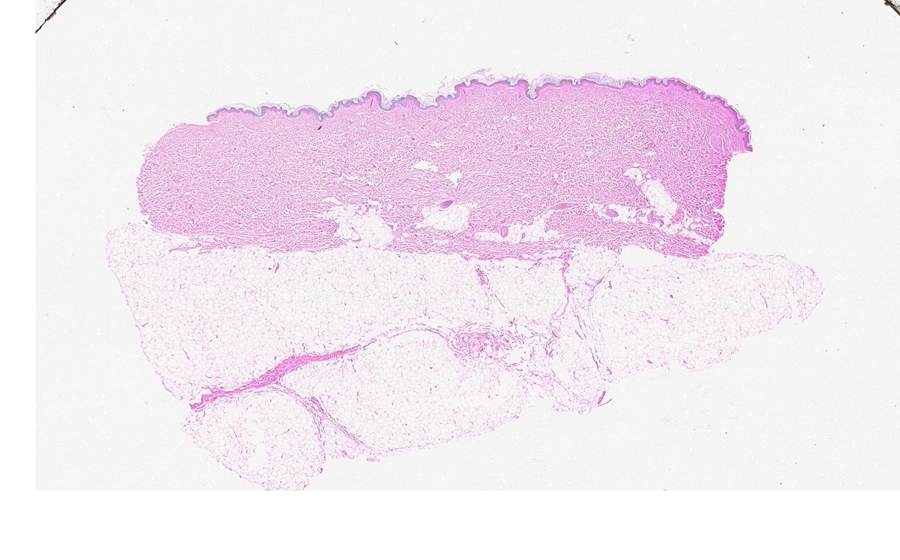

Slide 5: Liposarcoma

Histologic section of a liposarcoma. (click here to review normal tissue)

Image 1 - 50X

Section of normal scalp

Normal image 1 - 6.3X